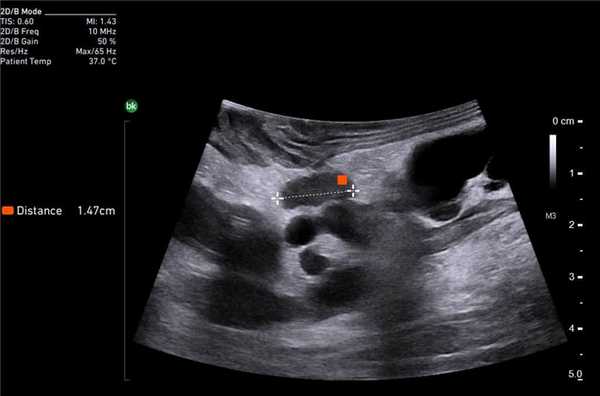

Клинический пример N2. Пациентка Р. находилась на лечении в ГУРОНЦ РАМН. При прохождении обследования был установлен диагноз рак толстой кишки. По данным ультразвуковой компьютерной томографии на фоне выраженной диффузной неоднородности паренхимы печени очаговые образования не определялись. При проведении ангиографии и компьютерной томографии так же убедительных данных за наличие метастазов в печень получено не было. При интраоперационном ультразвуковом исследовании были выявлены два очага, характерными особенностями которых являлись малые размеры (0,2 - 0,4 см), а так же нечеткость контуров и изоэхогенность структуры (рис. 1 а,б).

Рис. 1. Метастатические очаги (стрелки) в печени при интраоперационной ультразвуковой томографии.